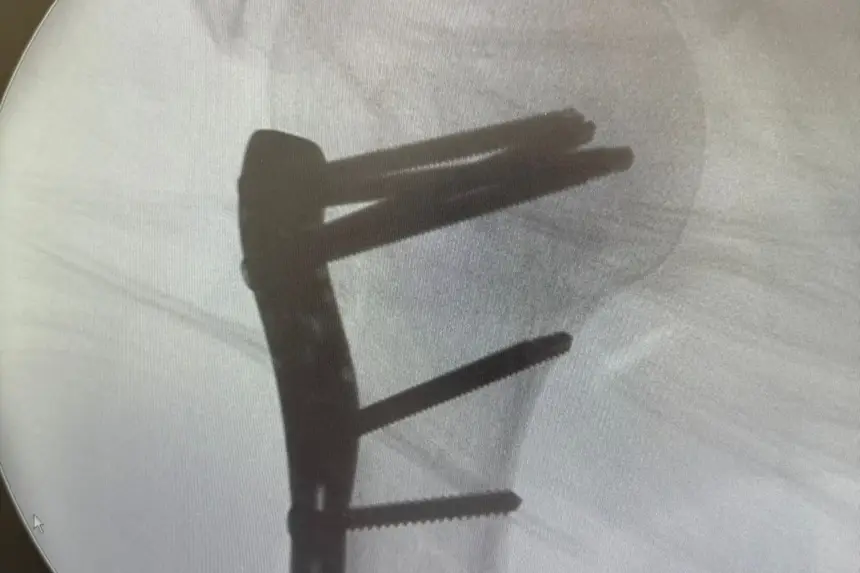

Entre os dias 23 de dezembro e 1º de janeiro, 109 pacientes vítimas de acidentes automobilísticos deram entrada no Hospital de Emergências (HE). Em um único dia, mais de 20 pessoas foram atendidas em decorrência desse tipo de ocorrência. Esse cenário resultou em um aumento significativo na demanda por cirurgias ortopédicas, principalmente em função de fraturas e traumas graves.

A maioria dos pacientes chegou à unidade com fraturas expostas, lesões em membros superiores e inferiores e traumas múltiplos, muitos deles causados por colisões envolvendo motocicletas. O fluxo intenso impactou diretamente a rotina do hospital, ocasionando corredores com pacientes aguardando entrada para cirurgia, enquanto equipes médicas e assistenciais atuavam de forma contínua para garantir um atendimento rápido e seguro.

De acordo com o secretário adjunto de Assistência Hospitalar, Rinaldo Martins, o volume de cirurgias ortopédicas aumenta de maneira considerável nesse período, e a prevenção no trânsito é fundamental para evitar riscos à vida.

Além dos acidentes de trânsito, o HE também registrou atendimentos relacionados a quedas, agressões e ocorrências domésticas típicas do período festivo. No entanto, os acidentes automobilísticos mantiveram-se como uma das principais causas de procedimentos cirúrgicos, com 102 atendimentos direcionados à área de ortopedia durante o fim de ano, reforçando o papel do hospital como a única unidade de emergências do estado, responsável pelos atendimentos de alta complexidade.